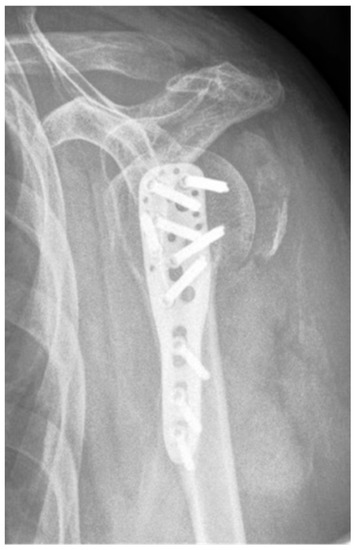

| Complication Type | Exemplary Images by X-rays or Pattern Images | Definition |

|---|---|---|

| 4 | ![]() | Complication Type 4a is based on the presence of AVN of the humeral head without concomitant destruction of the glenoid articular surface due to an associated screw cutout through the humeral head cortex. |